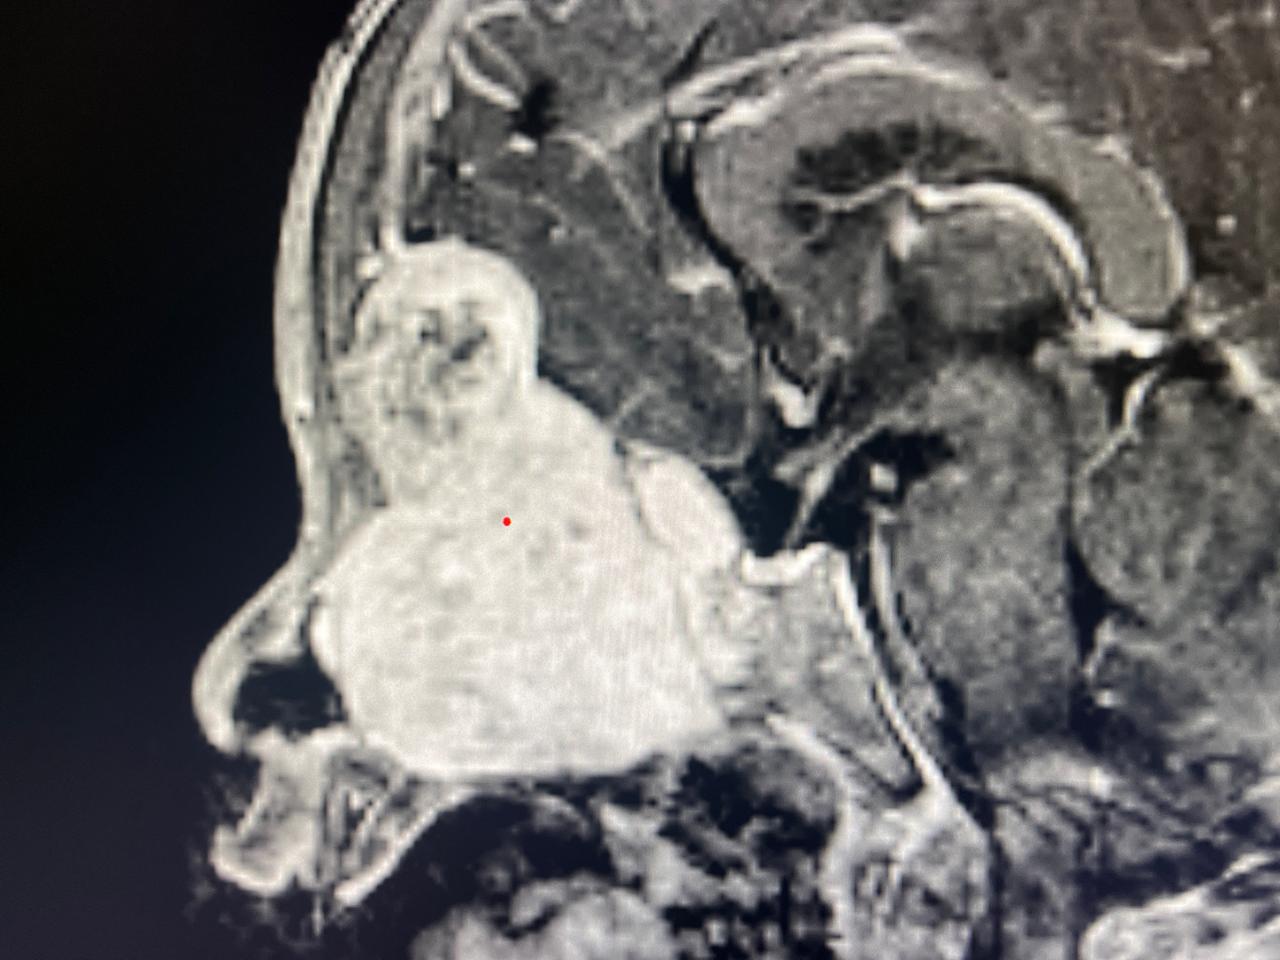

Sidhivinayak taimes Shimla। In a groundbreaking medical achievement, surgeons at PGIMER, Chandigarh have successfully removed a giant 7 cm skull base meningioma from a 2-year-old child using only endoscopic techniques, marking a world first. The young patient from Sonipat, Haryana, had been suffering from a protruding left eye, restricted eye movement, snoring, and a nasal mass. Imaging revealed a massive tumor extending from the skull base into the nose, sinuses, orbit, and brain. Given the child’s age and the tumor’s complexity, the surgery posed extreme risks, including blood loss, hypothermia, and fluid imbalance.

A specialized team of neurosurgeons, ENT specialists, anesthesiologists, and nursing staff collaborated on the meticulous 9-hour procedure. Using advanced endoscopic tools, angled instruments, navigation systems, and innovative techniques to access the tumor through the nose, the team successfully removed it entirely without open surgery. Post-operative scans confirmed total excision, and the child is recovering well. Experts say this milestone underscores the world-class surgical expertise and innovation at PGIMER, setting a new benchmark in pediatric neurosurgery.